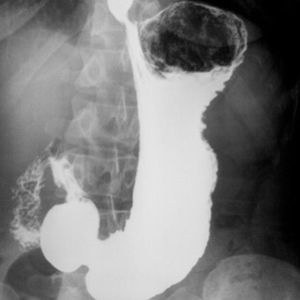

X-Ray examination of the stomach

X-Ray examination of the stomach, by using a high atomic-weight contrast medium called Barium Sulfate, orally administered. By using contrast medium, estimation of the size, shape, and pathological changes are possible by radiologists.